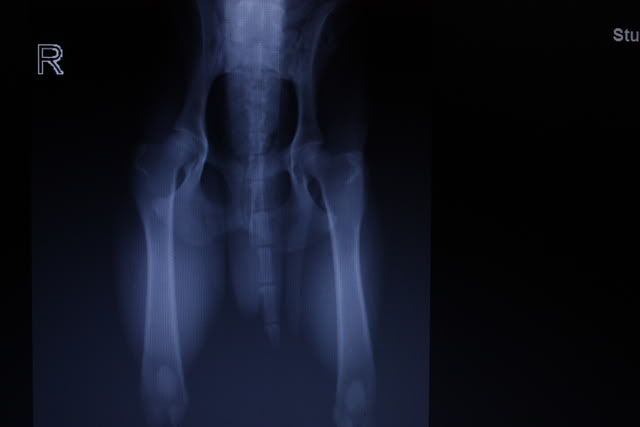

Er werden rontgenfoto's gemaakt van de heupen en de ellebogen.

Gelukkig is er een goede uitslag, zowel de heupen als de ellebogen zien er uitstekend uit.

Ik heb de foto's meegekregen met een mooi programma waarin ik ze kan open en inzoomen enzo.

Daarom heb ik maar een foto ervan gemaakt terwijl ik ze op de computer heb.

Het is dus niet echt heel duidelijk, maar geeft in ieder geval een idee.